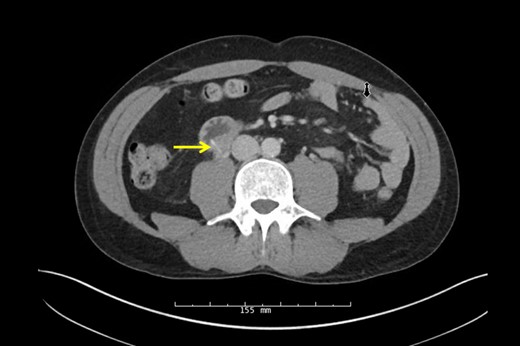

Urology performed a right retrograde pyelogram demonstrating a point of obstruction in the proximal ureter with no contrast extravasation. A guide wire and stent were passed through the obstruction into the hydronephrotic right kidney without difficulty. Following successful stent insertion, fluoroscopy was used to confirm the location of the FB at the junction of the second and third portion of the duodenum. A full Kocher maneuver was performed and the duodenum and ureter were separated. A small, linear, FB was identified projecting from the posterior third portion of the duodenum into the ureter (Fig. 3) and extracted without injury (Fig. 4). The patient's original abdominal pain resolved after the surgery. He was able to tolerate a diet and be discharged on postoperative day 4.

Intraoperative identification of the FB from the duodenum to the ureter.